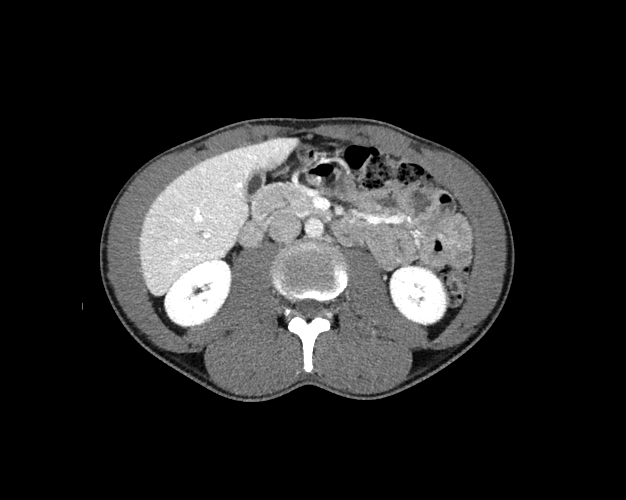

Body

Covers abdominal CT anatomy.